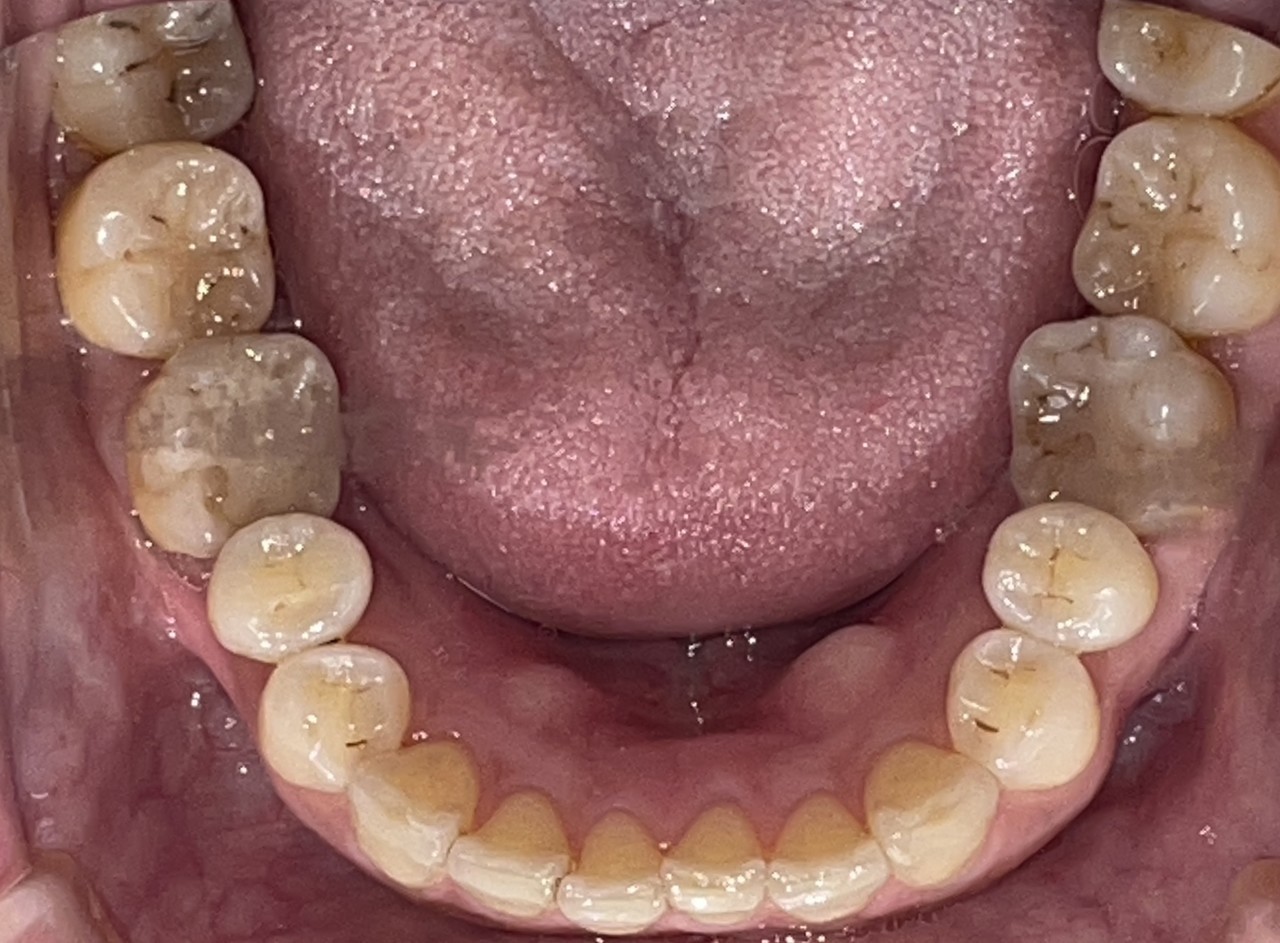

Before

After

矯正の種類 / invisalign GO

年齢・性別 / 30代女性

主訴  /  叢生 かみ合わせ

治療期間 / 17ヶ月

費用 / 簡易検査 5,000円(税別) 精密検査 30,000円(税別)

両額マウスピース 450,000円(税別)  両額リテイナー料 60,000円(税別)

※マウスピース交換時別途調節料3,000円(税別)

副作用 / 口内炎・歯の移動に伴う痛み・知覚過敏 ※数日で収まる場合が多いです

リスク / 後戻り防止の為、夜のみマウスピースで保定を指示